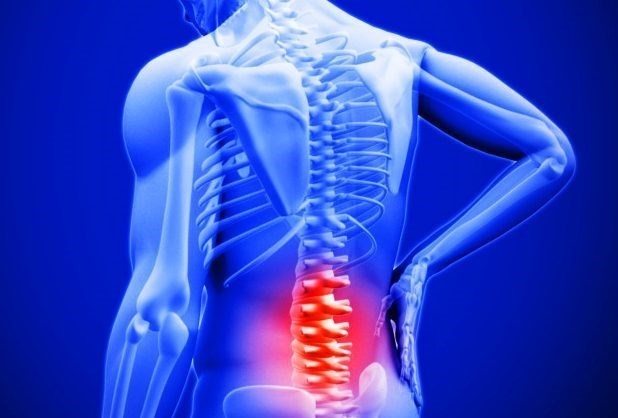

به گزارش گروه بازرگانی خبرگزاری تسنیم، به یاد داشته باشید که مراکز درمانی کلینیک تخصصی درد در درمان کمردرد بسیار کمککننده خواهند بود. کمردرد یکی از مشکلات شایعیست که مطمئنا هر فردی حداقل یکبار در طول زندگی خود تجربه میکند.

غیر ممکن است که بتوانیم دقیقا علت اصلی کمردرد را بگوییم. زیرا دلایل بسیاری وجود دارد که سبب ایجاد این عارضه میشود. اگر کمردرد شما یک بیماری مهم و اساسی باشد، میتواند بهدلیل موارد زیر ایجاد شود:

- فشار روی نخاع

- شکستگی مهره

- دیسک

- فشار بر نخاع

- تومور نخاعی

- عفونت در ستون فقرات